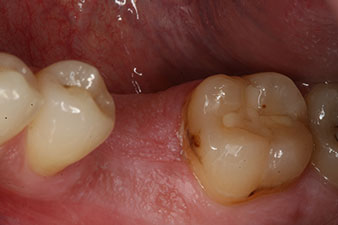

incompletely ossified alveolus

Fig. 2: Six weeks later there was an incompletely ossified alveolus in the region of the mesial root.

However, six weeks after the extraction incomplete ossification was found after preparation of the mucoperiosteal flap in the region of the former mesial alveolus.